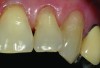

A 55-year-old woman presented with root decay along the left lateral incisor (tooth No. 10) and canine (tooth No. 11) (Figure 1). It was proposed that invisible Class V restorations be placed using an MMID procedure. There are several keys to attaining a successful invisible Class V restoration. Proper understanding of composite resin shade selection, preparation design, and sequence of composite resin layering are important to achieve an ideal blending of the composite resin to the existing tooth. Correct finishing and polishing technique is equally essential in obtaining a seamless esthetic restoration.3,11

Shade selection is always completed before initiating treatment; this is important to develop the proper shade-layering sequence. Composite shades were placed directly on the tooth and shades that matched the areas of the tooth being restored were chosen (Figure 2). To achieve an invisible Class V restoration, a more complex layering process is needed to blend the composite resin.